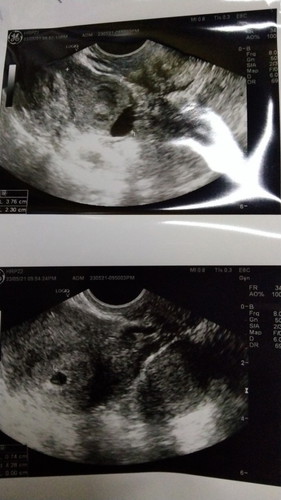

Scan 7 minggu belum nampak baby dalam kantung.adakah kandungan saya bermasalah?

Scan perut dah 4 kali masih Tak dapat lihat kandung. Scan ttanvransviginal dah 2 kali tp doktor bgt xnampak baby dlm kantung Dan mungkin akan gugur

Nampak mcm ada dot kecil dlm kantung.. Sy 10minggu pun x nmpk jelas sgt.. Yakin dgn Allah.. InshaAllah ada rezeki sis

Sllunye 7week nmpk mcm seketul drh beku tue.. tp kecik.. tp pkir baik2 je sis.. tggu la 9week ke.. g scan plk..